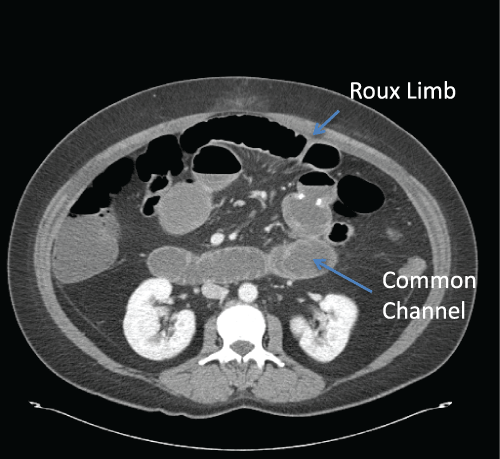

SBO following bariatric surgery can be divided into early and late obstruction. While some authors have attempted to standardize the definition of “early” and “late” obstructions [25], there is no clear consensus. Bariatric patients presenting with SBO in the immediate post-operative period usually report abdominal discomfort, bloating, nausea and vomiting. This usually results, in the immediate post-operative period, from technical issues with the construction of the JJ, trocar site hernias or bleeding with intra-luminal blood clots. Internal hernias can also result in SBO but they usually present later and those will be discussed in other chapters [26,27]. Bilious vomiting usually indicates obstruction distally in the common channel (Figure 3) while non-bilious vomiting is more indicative of a proximal obstruction (Figure 4). These patients may be tachycardic and hypoxic and therefore gastrointestinal leakage and bleeding must also be considered.

Figure 3: CT scan demonstrating dilated common channel and Roux limb

following a Laparoscopic Roux-en-Y-Gastric Bypass. This patient presented

with abdominal pain and bilious vomiting.

Figure 4: CT scan demonstrating dilated Roux limb secondary to an

obstruction of the JJ. This patient developed abdominal pain, nausea and

non-bilious vomiting two days following the Laparoscopic Roux-en-Y-Gastric

Bypass.